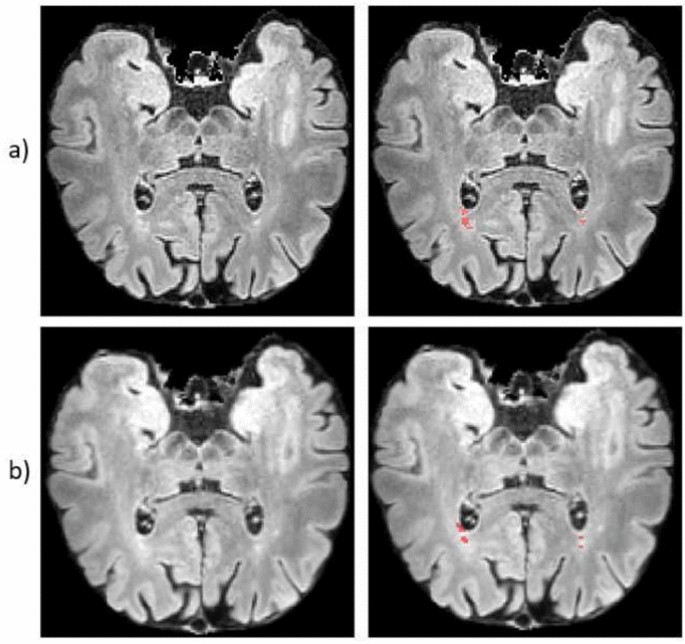

For the segmentation of hyperintense lesions on T2-FLAIR images using LST (as shown in Fig. 4), the Dice Index achieved values of \(0.713 \pm 0.0095\), while the IoU reached \(0.562 \pm 0.113\).

Axial view of hyperintense lesions segmentation with LST between two protocols: conventional (row a) and accelerated (row b). In the first column are presented the T2-FLAIR scans, in the second lesions segmentations.